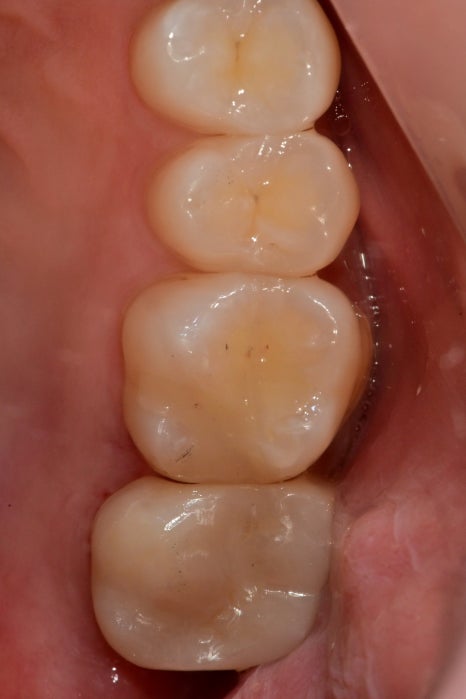

왼쪽 아래의 과거의 수복물이 탈락된 상태에서

방치된 상태에서 내원해 주셨습니다.

환자분께서는 신경치료를 받지 않고 치료해서 지내고 싶다고 하셨습니다.

오래된 접착제, 충치에 의해 영향받은 건강하지 못한 치질까지

제거를 모두 해주니 신경이 노출돼있었고

괴사되진 않았지만 노출 범위가 넓었고,

주변을 깨끗하게 소독하고 MTA를 사용해야 하기 때문에

노출된 신경 잔사를 마저 제거해 주고 지혈을 했습니다.

갈색빛이 나지만 건강한 치질이기 때문에 남겨놓은 상태로

소독, 지혈 후 적용

신경을 안정시켜주는 MTA는 강도가 약하기 때문에

그 상부로는 단단한 레진이라는 재료를 덮어줘

치아를 보강하고 그 위에 크라운 치료까지 마무리되었습니다.